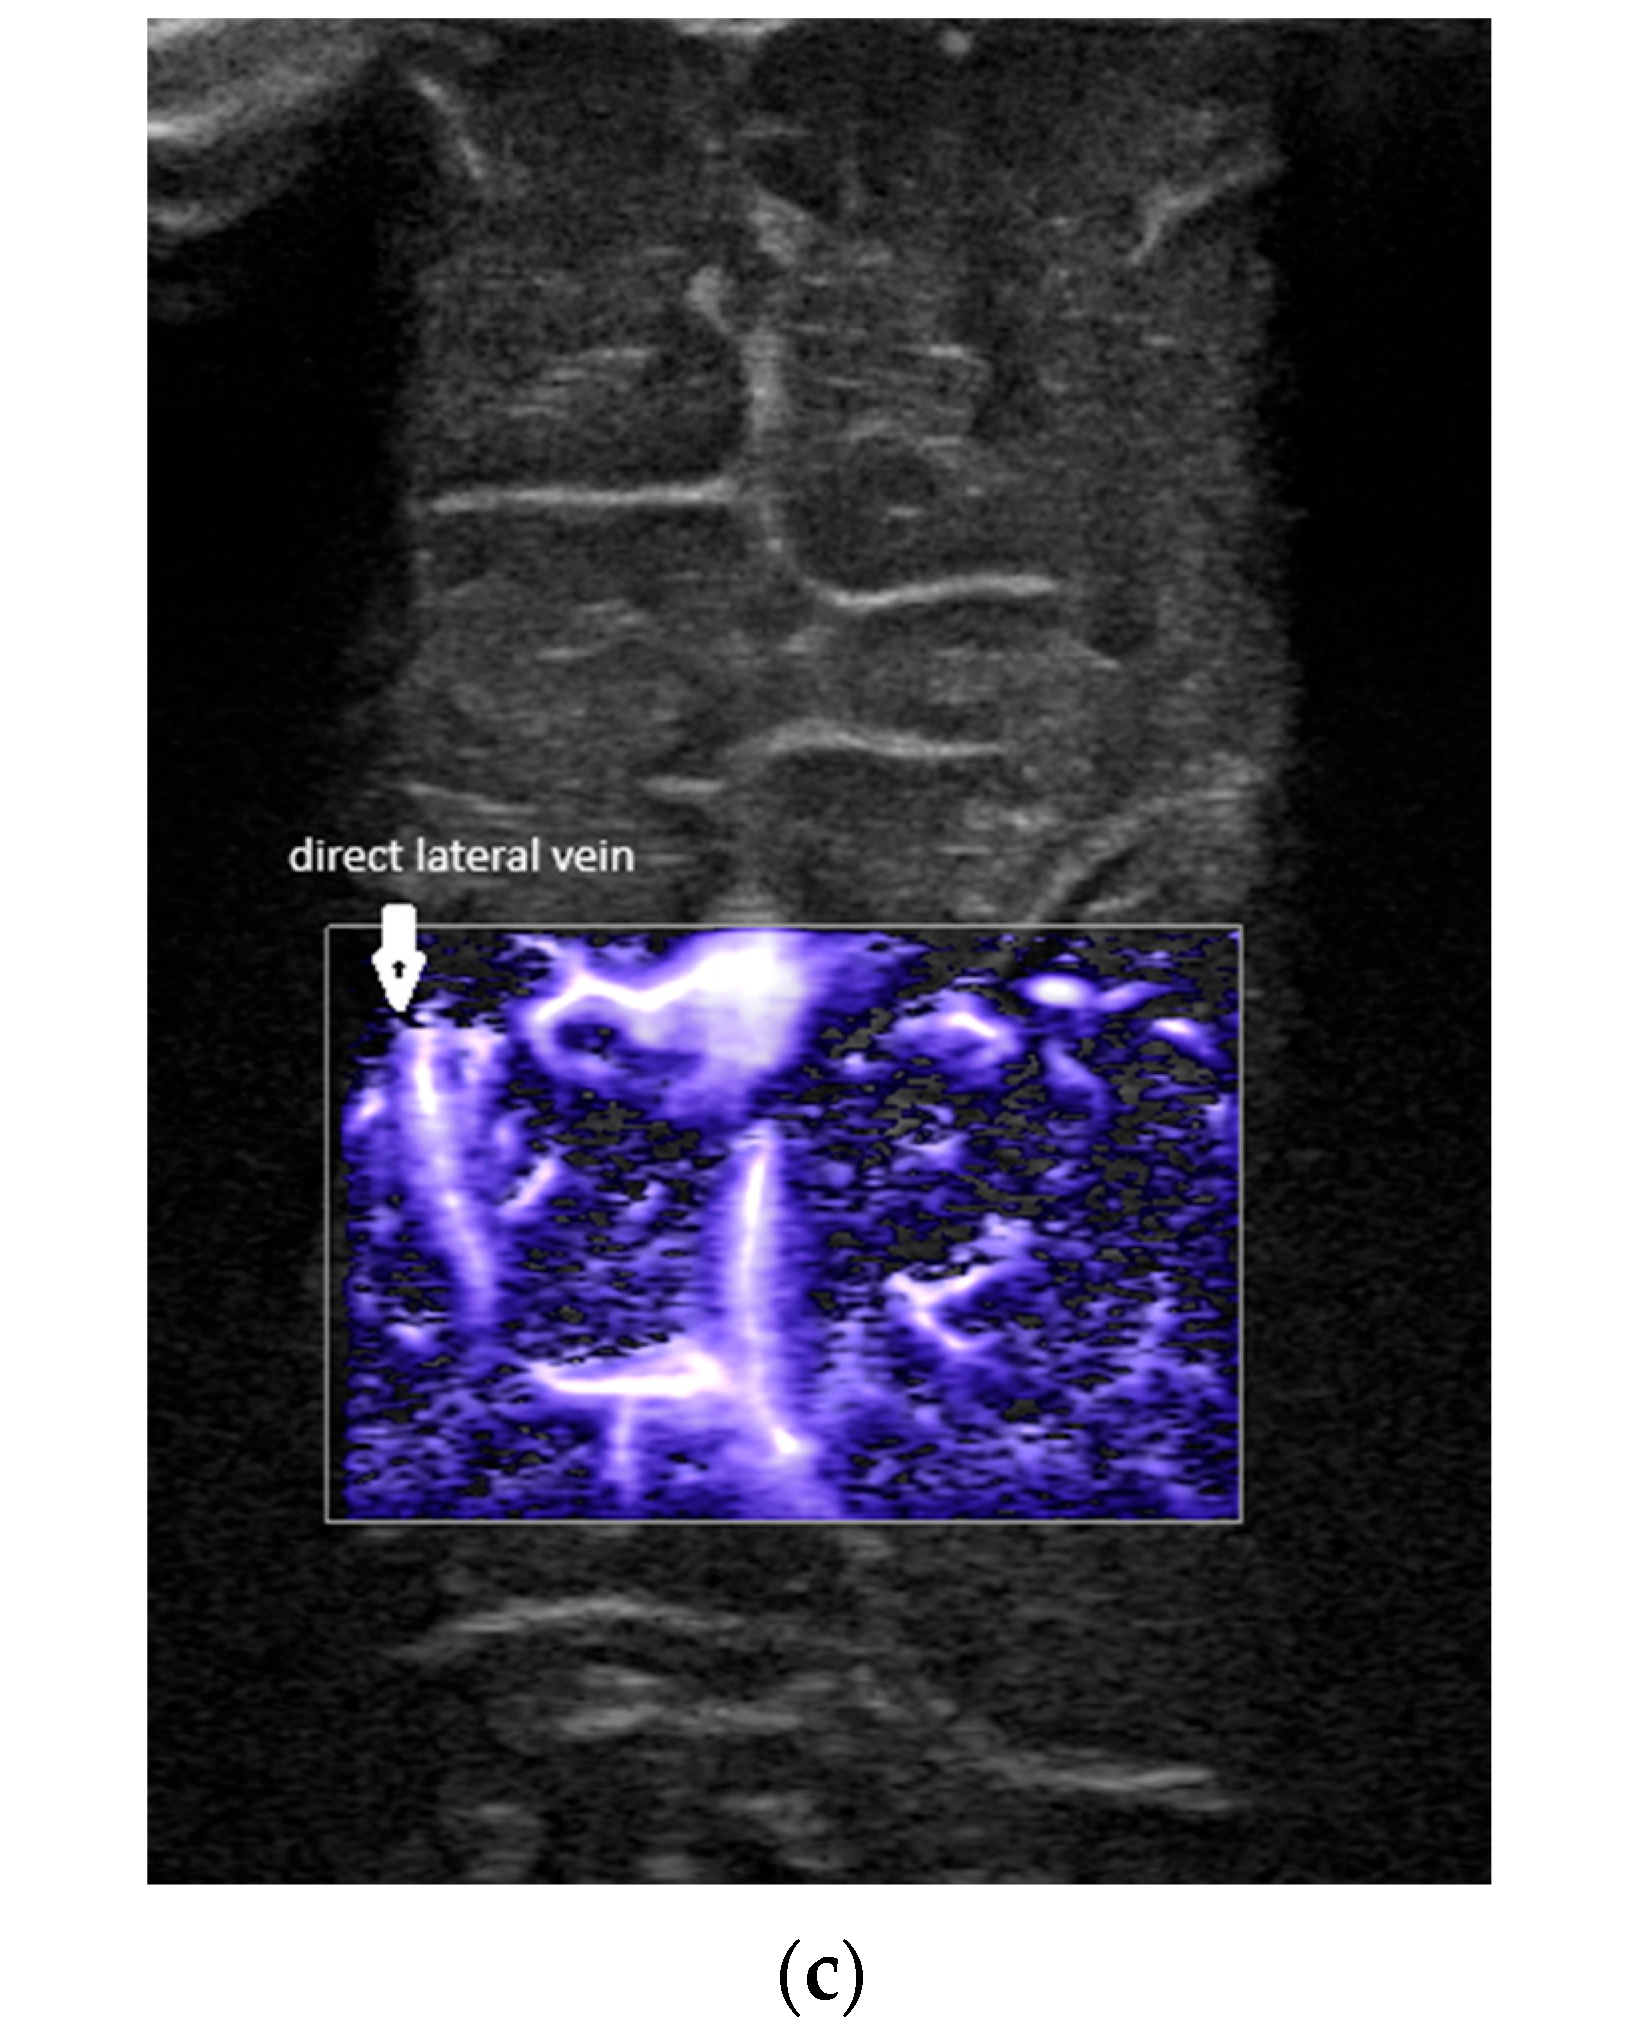

- Confluence at the level of the foramen of Monro (Figure 2).

- A lack of identification of the confluence—wherein the terminal vein was absent on one or both sides—an example is the case presented in Figure 3, where the terminal vein was most probably draining in a direct lateral vein on the left side.